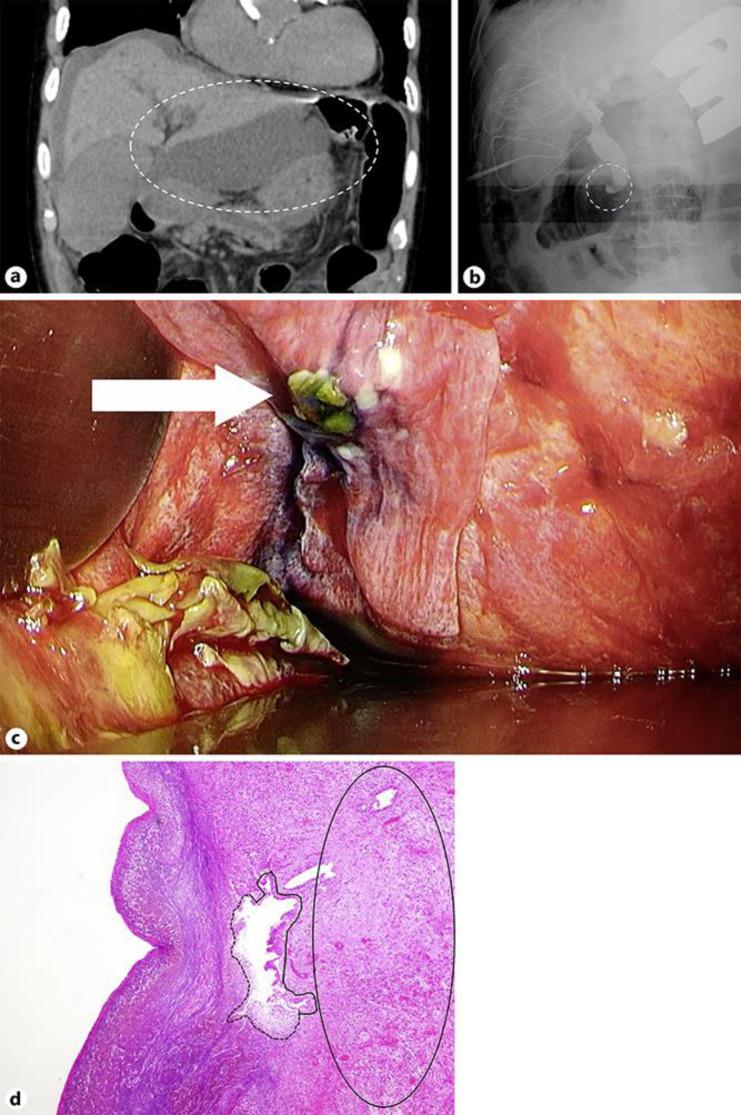

Spontaneous bile duct rupture is a rare condition in adults, with only 70 cases reported. Increased bile duct wall pressure may lead to rupture and biliary peritonitis. In this patient, the bile duct ruptured in the hepatic left triangular ligament. A 91-year-old man underwent endoscopic retrograde cholangiopancreatography for choledocholithiasis and endoscopic retrograde biliary drainage (ERBD) placement. One week later, removal of the ERBD and common bile duct stones and an endoscopic sphincterotomy (EST) were performed. Four days later, the patient had abdominal pain, increased inflammatory reaction, and jaundice. Abdominal computed tomography showed ascites, bile duct dilatation and fluid collection under the liver (10 cm in diameter). Emergency surgery was performed to drain the fluid. On laparotomy, encapsulated biliary ascites was seen. To search for the site of the leak, after cholecystectomy, a tube (C-tube) was inserted into the common bile duct via cystic duct stump. Because of uncontrollable bleeding, after packing with surgical gauze, the operation was temporarily stopped. The next day, reoperation was performed. Intraoperative cholangiography with contrast dye revealed the perforation site in the left triangular ligament and a partial resection was performed. Bile excretion from the C-tube was subsequently observed, but the patient's jaundice did not improve. Although endoscopic retrograde cholangiopancreatography revealed that the EST site was normal, ERBD was placed again, and the jaundice gradually improved. Although EST was performed in this case, biliary peritonitis resulting from spontaneous bile duct rupture occurred. This case was very informative because biliary perforation may occur even after EST.

自发性胆管破裂在成人中是一种罕见疾病,仅有70例报道。胆管壁压力升高可能导致破裂及胆汁性腹膜炎。在该患者中,胆管在肝左三角韧带处破裂。一名91岁男性因胆总管结石接受了内镜逆行胰胆管造影术及内镜逆行胆管引流(ERBD)置管。一周后,拔除了ERBD并取出胆总管结石,同时进行了内镜括约肌切开术(EST)。四天后,患者出现腹痛、炎症反应加重及黄疸。腹部计算机断层扫描显示有腹水、胆管扩张及肝下积液(直径10厘米)。遂进行急诊手术引流积液。剖腹手术时,可见包裹性胆汁性腹水。为寻找渗漏部位,胆囊切除术后,经胆囊管残端将一根管子(C管)插入胆总管。因出血无法控制,用手术纱布填塞后,手术暂时停止。第二天,再次进行手术。术中经造影剂胆管造影显示左三角韧带处有穿孔部位,遂进行了部分切除术。随后观察到有胆汁从C管排出,但患者黄疸并未改善。尽管内镜逆行胰胆管造影显示EST部位正常,但再次置入了ERBD,黄疸逐渐改善。尽管该病例进行了EST,但仍发生了自发性胆管破裂导致的胆汁性腹膜炎。该病例极具参考价值,因为即使在EST后也可能发生胆管穿孔。